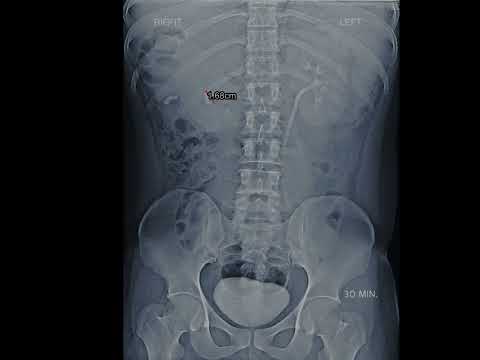

Video: KUB X ray Show Kidney Stone #aiims #shortsvideo #biology #doctor #mbbs